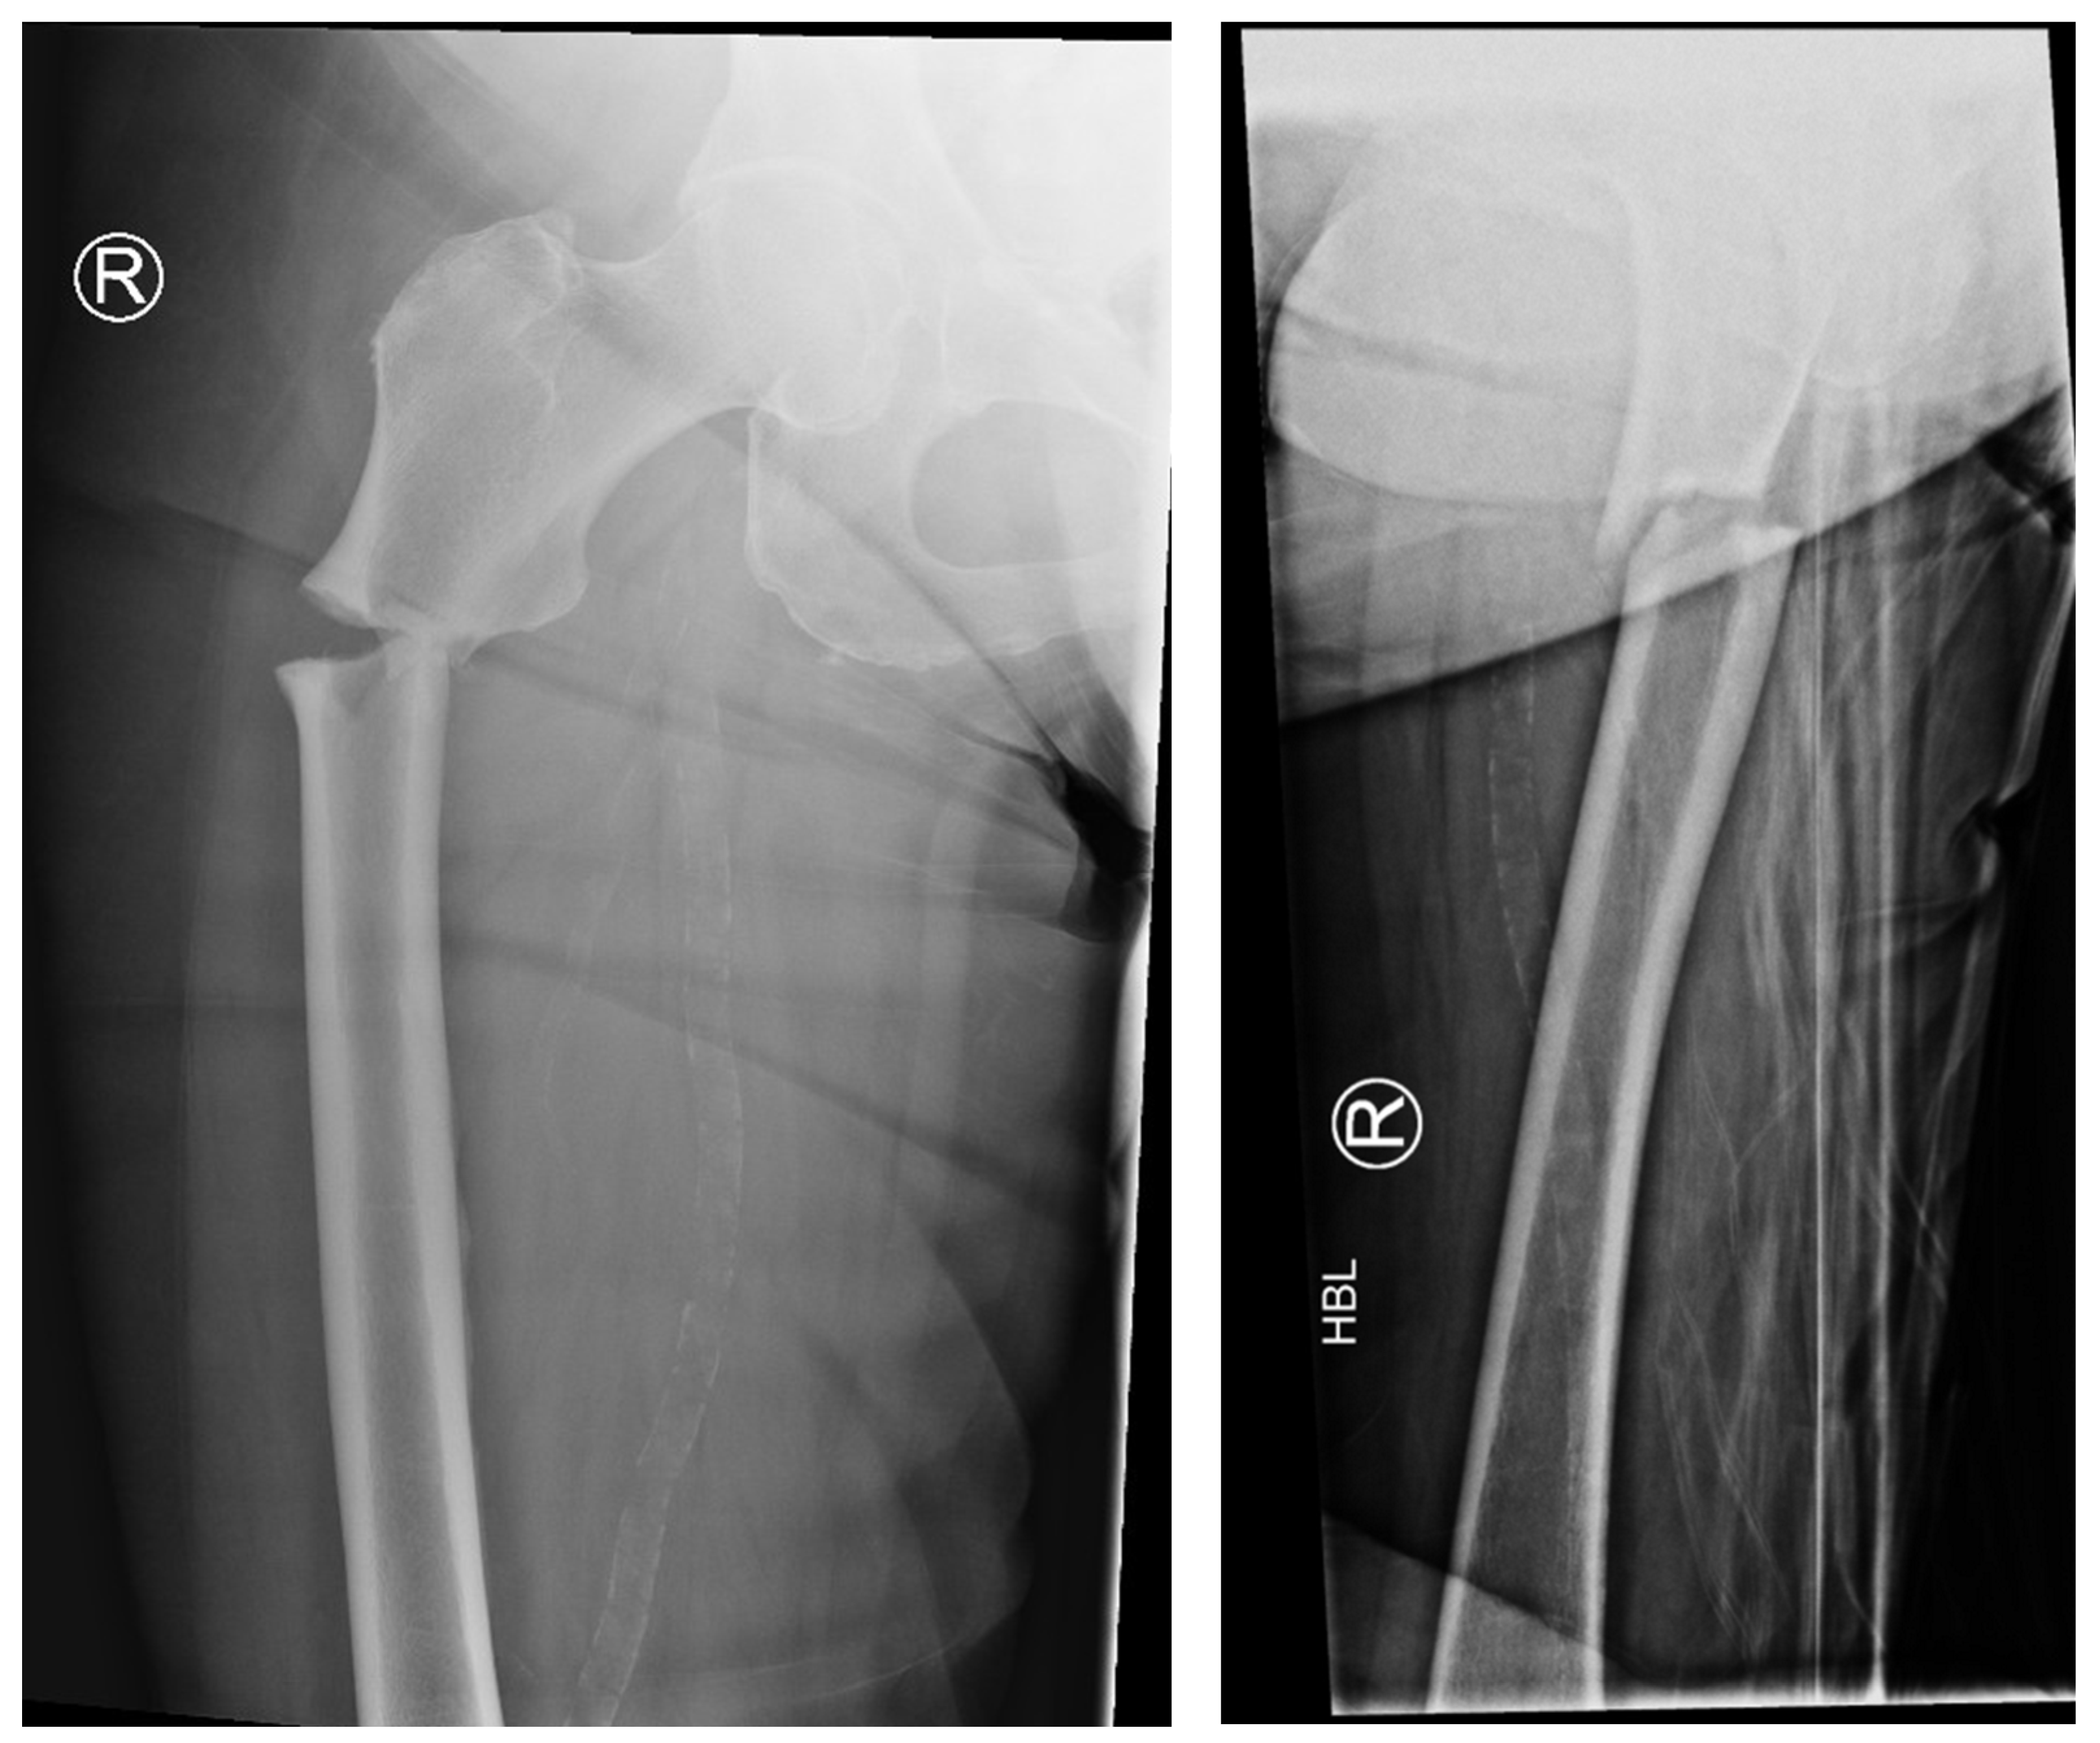

The following radiographs present the initial radiographs from the day of injury along with those obtained during the final OPD follow-up of the patient. The sequence presents radiographs demonstrating full radiological union (Scheme 1 and Scheme 2) and X-rays with no evidence of fracture healing at the final OPD follow-up (Scheme 3 and Scheme 4).

Scheme 1. X-ray of right hip AP view (left) and lateral view of right proximal femur (right) of atypical subtrochanteric fracture—September 2023.

Jcm 14 02858 sch001